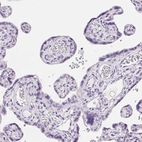

Immunohistochemistry analysis in human fallopian tube and placenta tissues using Anti-C20orf85 antibody. Corresponding C20orf85 RNA-seq data are presented for the same tissues.